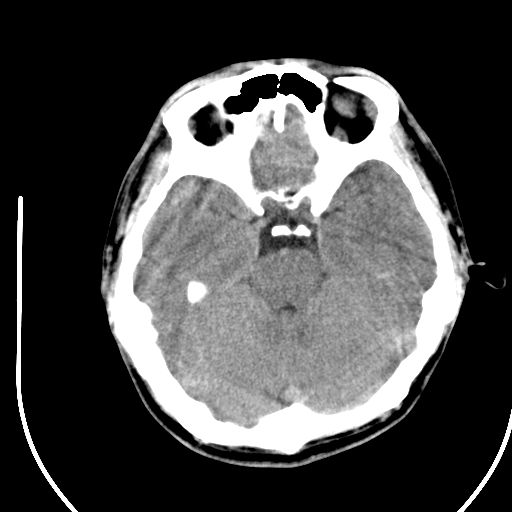

标题: CT28158:男,27Y。头痛数月,左顶叶血管瘤。 [打印本页]

标题: CT28158:男,27Y。头痛数月,左顶叶血管瘤。

海绵状血管瘤

考虑左顶叶海绵状血管瘤,建议mr检查。

考虑血管畸形,因其周可见水肿,不除外感染性病灶。建议mri检查。